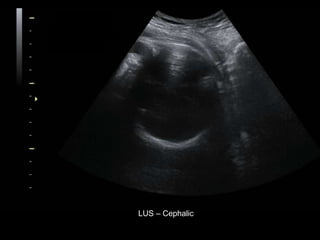

โ€ข 36 yo female 30.5 weeks pregnant

โ€ข Referred with โ€žmultiple fetal anomaliesโ€Ÿ for

fetal ultrasound

LUS โ€“ Cephalic